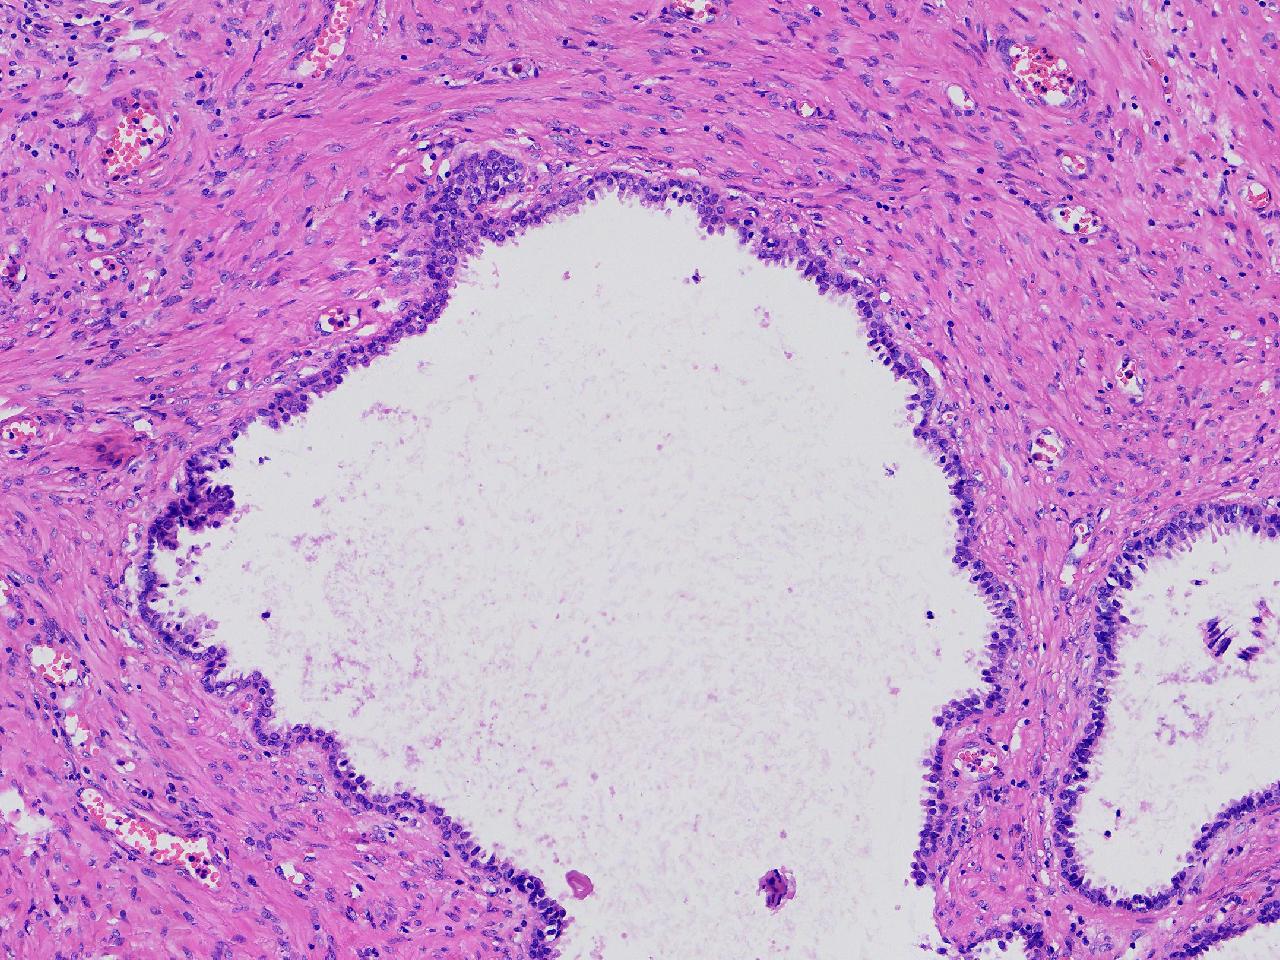

良性前列腺增生?

男,68岁,排尿困难半年余。行前列腺前切术。

前列腺电切标本

灰粉色条索状软组织多块,4X3X3厘米。

考虑为良性前列腺增生症

良性增生

BPH.